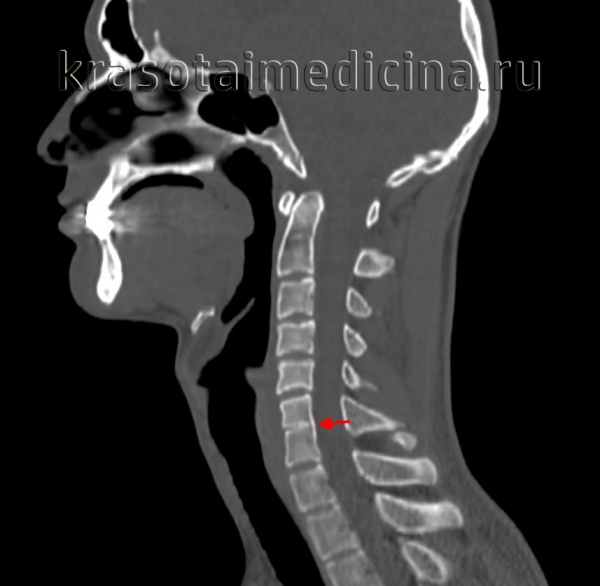

2. КТ признаки краниостеноза:

• КТ, костное окно:

о Фиброзное/костное сращение шва по типу «мостика» ± «клюва»

о Форма головы определяется видом вовлеченного шва (швов)